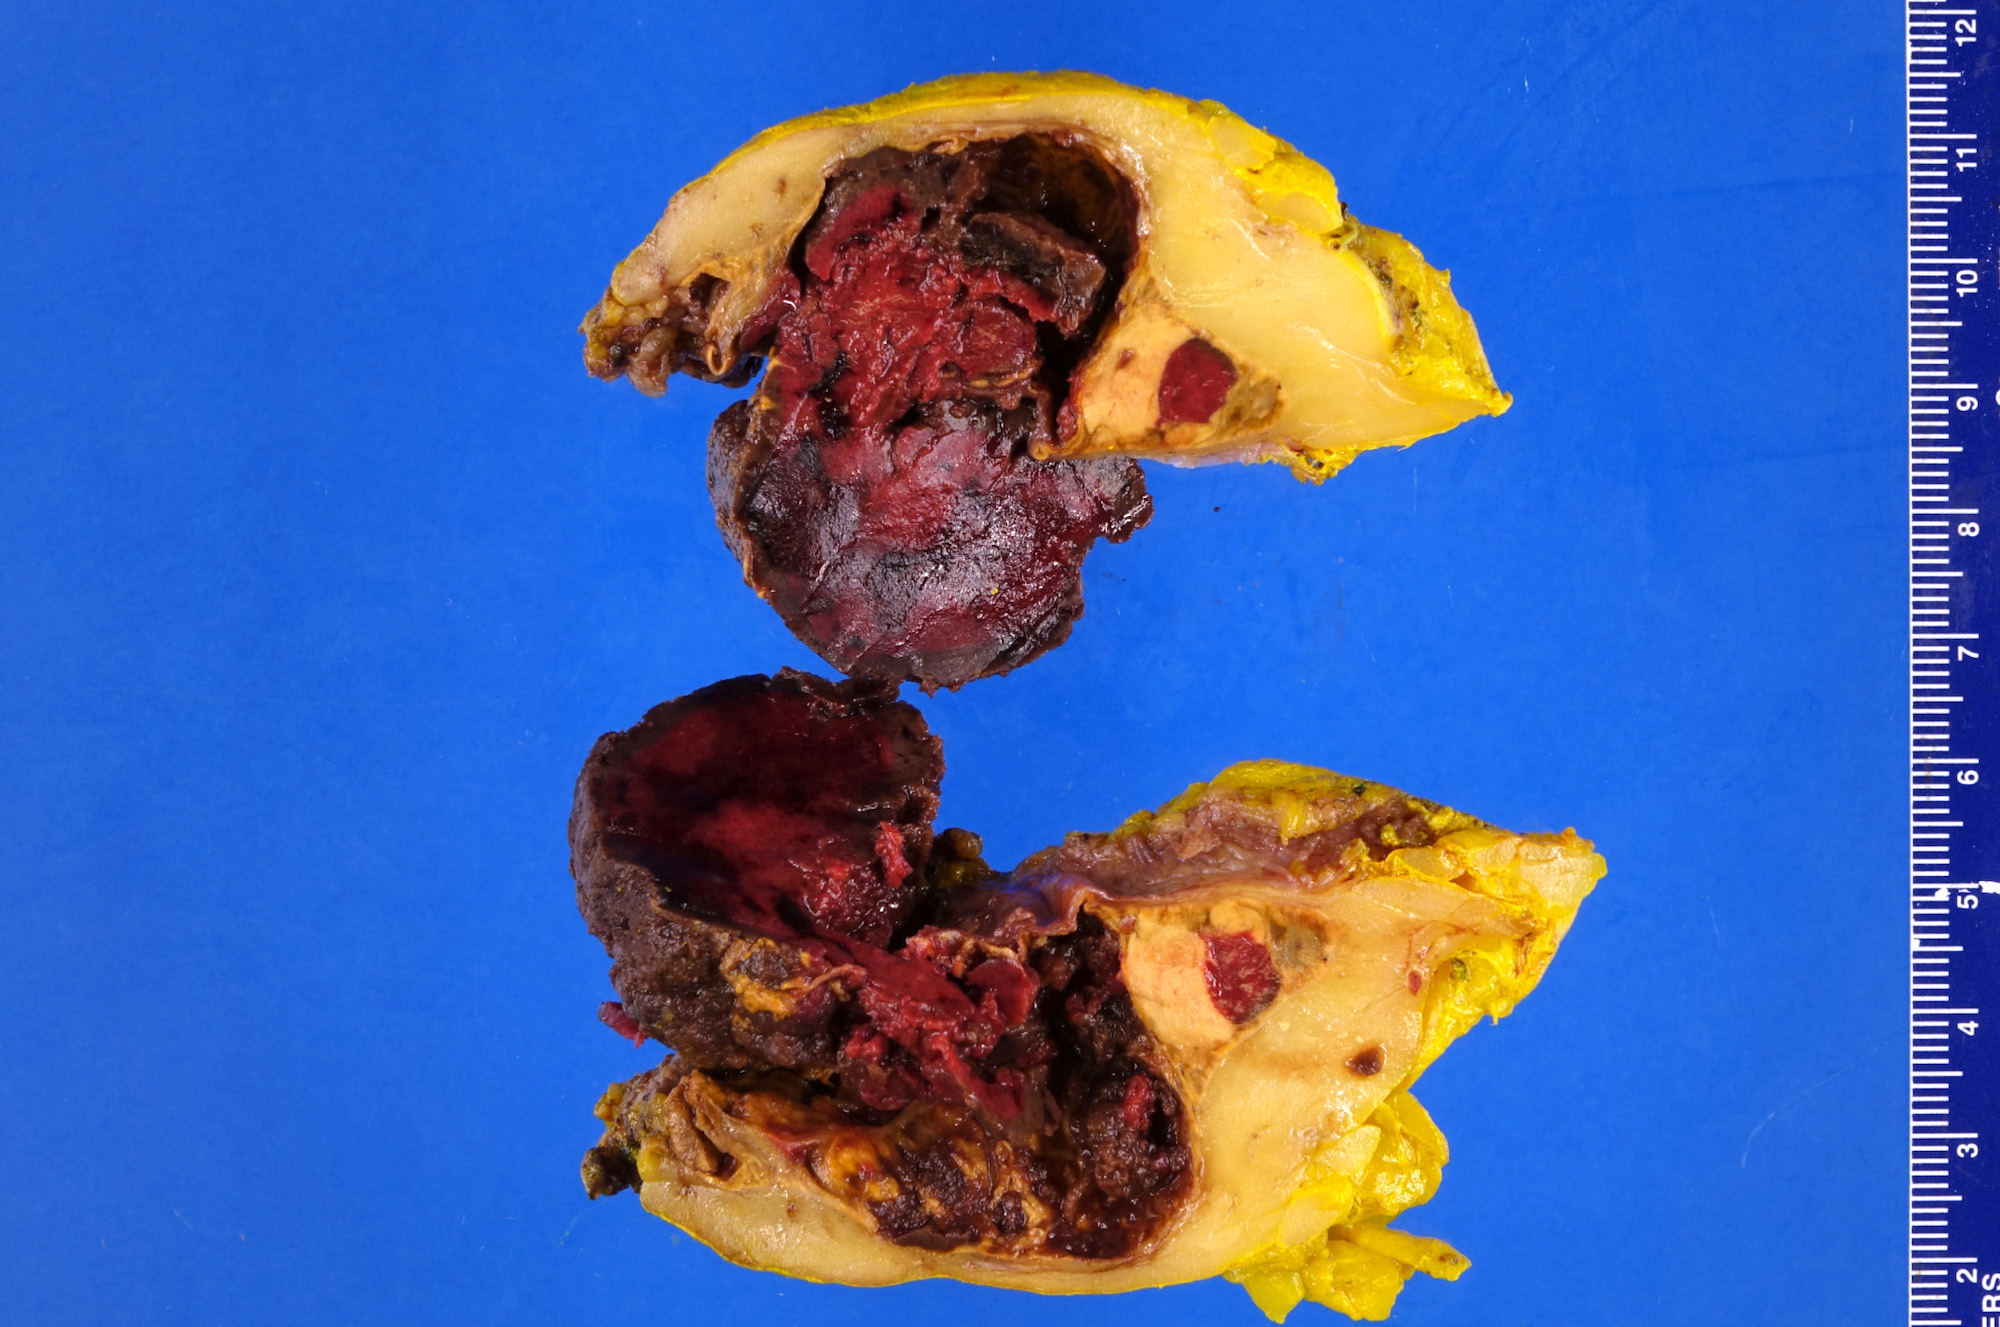

Gross description

- Well demarcated, unencapsulated, yellow (mature fat) to red (hemorrhage) nodule depending on the composition; if large, hemorrhage and infarction are common

- Mean size is 10 cm (0.5 - 43 cm); weight may be up to 11 kg

Gross images

Contributed by Debra L. Zynger, M.D. and Anil Parwani, M.D., Ph.D.